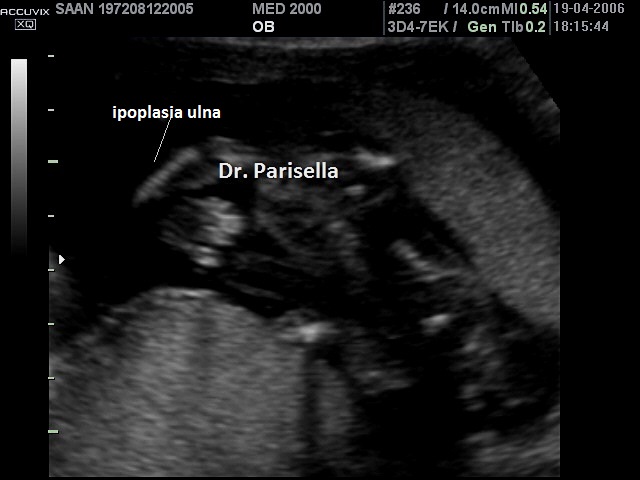

Sindrome o Complesso Femore-Fibula-Ulna OMIM 228200

E' una rara sindrome malformativa caratterizzata da difetti, ipoplasia o aplasia, di femore, fibula e ulna ai quali possono associarsi difetti delle dita.  I difetti delle dita, se presenti, interessano il lato ulnare e/o quello fibulare. Viene classificata in quattro gruppi in base all'interessamento di uno, due, tre o quattro arti.

L'interessamento di femore, fibula ed ulna è caratteristico ma possono essere interessate anche le altre ossa lunghe: la mano (aplasia), la tibia (ipoplasia) e l'omero (ipoplasia).

La coesistenza dell'interessamento di questi tre segmenti ossei da soli è sufficiente a porre la diagnosi di Sindrome o Complesso Femore-Fibula-Ulna, indipendentemente dall'interessamento o meno di altri segmenti ossei. La triade femore-fibula-ulna è patognomonica della patologia.